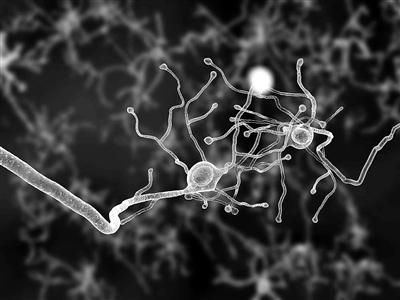

| 图片来自网络 |

科技日报华盛顿11月16日电 (记者刘海英)众所周知,每个人的指纹都是独一无二的,可作为个人的身份识别标记。而美国卡内基梅隆大学15日发布新闻公告称,该校领导的研究团队使用一种新的成像技术,证实了每个人的大脑连接结构与指纹一样,也是独一无二的,而且这种特异性还会随着时间的推移而发生变化。研究团队在《科学公共图书馆·计算生物学》杂志上发表文章称,对人脑连接结构特异性的理解将有助于人脑功能及相关疾病的研究。

该团队使用非侵入性的磁共振弥散成像技术,对699人大脑白质通路的逐点连接状况(即所谓的本地连接,与各脑区之间的连接相对应)进行了测量。结果显示,人脑本地连接结构具有高度特异性,每个人的连接结构都是独一无二的,可以如指纹一样被看作是一个人的身份标记。为测试这种特异性,研究团队进行了17000多次识别试验,分辨两个连接结构是否属于同一人,其准确率近乎百分之百。

此外,研究人员还发现,即使是同卵双胞胎,他们的大脑连接模式也只有12%的相似性,而且随着时间推移,连接模式会逐渐改变,越来越具有特异性,平均变化速率达到每100天改变13%。

研究人员表示,许多科学家认为人的大脑连接模式是独一无二的,而此次他们的研究证实了这一点。新研究表明,人脑连接结构的特异性会随时间推移而变化,这意味着一个人的许多生活经历,包括一些疾病、环境因素等,都会在某种程度上反映到大脑连接模式上。因此,对大脑连接结构特异性的理解将有助于研究遗传、环境因素以及个人经历对大脑的影响,它会是一种潜在的医学生物标记,为研究人类大脑的功能和一些脑疾病打开一扇门。